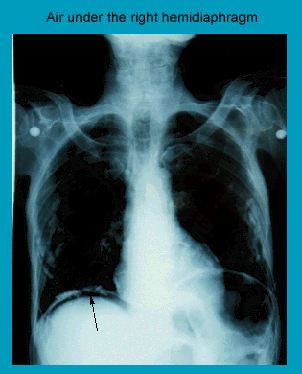

Air under the diaphragm on chest radiograph